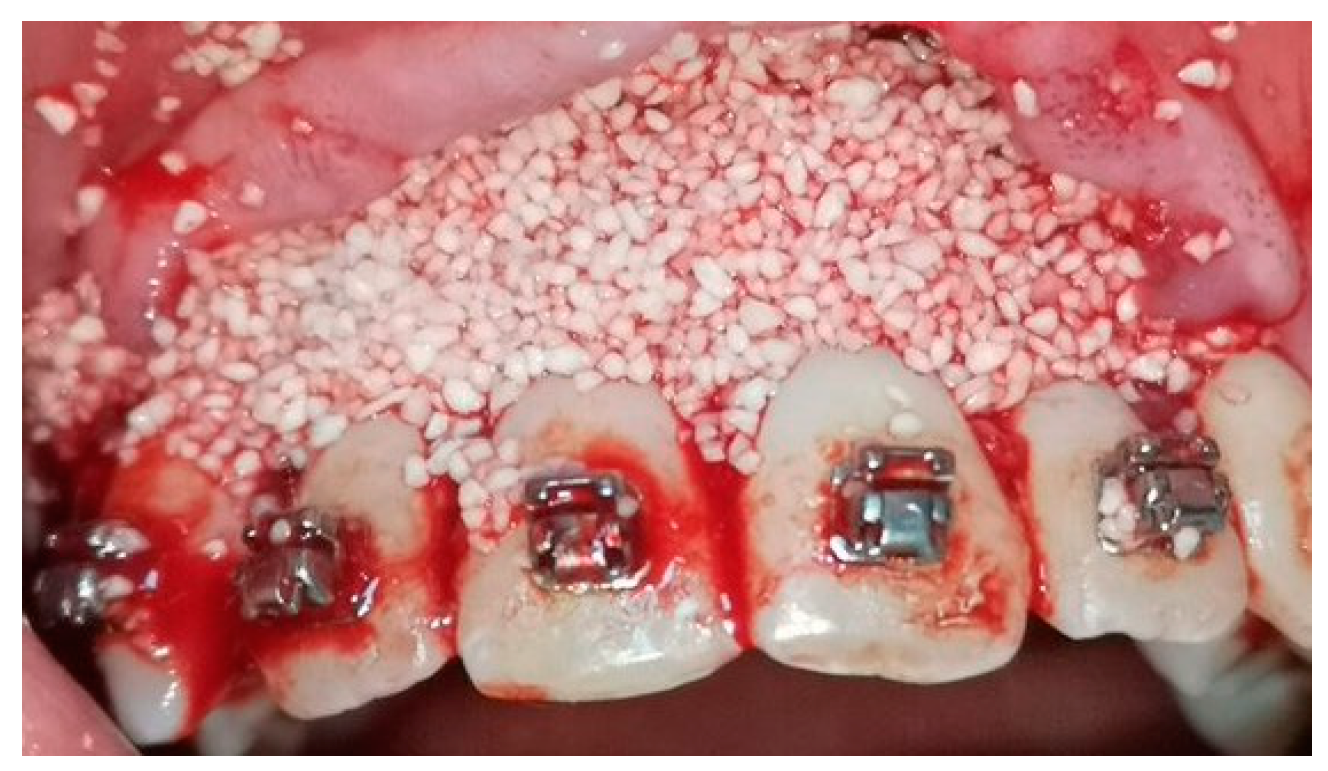

2.5. Surgical Phase

2.6. Collection of the Radiological Data